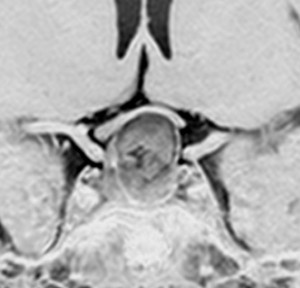

尿崩症で発症した小さな腫瘍

尿崩症で発症した9歳男児にみられたxanthogranuloma of the sellar resion。左はT1強調画像で高信号,右はT2強調画像で低信号であり,肉芽腫の特徴がみられます。のう胞部分はT2強調画像で,高信号になります(右図)。このような小さな頭蓋咽頭腫やラトケのう胞が尿崩症を呈することはまれですが,黄色肉芽腫の場合は小さくても症候性となることが多いです。神経下垂体組織が炎症性に破壊されるからと考えられます。